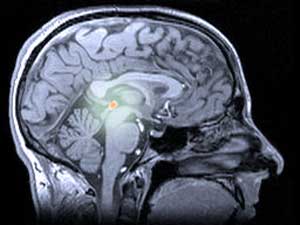

Chez l’humain et les autres animaux, la mélatonine est produite par la glande pinéale (prononcée ‘pi-né-ale’), une structure plutôt mystérieuse située profondément dans le cerveau. La glande pinéale est parfois appelée ‘troisième œil’, car chez certains lézards, elle est située sur le dessus de la tête et sert à détecter les ombres des prédateurs volants.

La lumière et l’obscurité sont également importantes pour la glande pinéale humaine et la mélatonine qu’elle produit. La glande pinéale reçoit des signaux lumineux des yeux et libère la mélatonine quand il fait sombre. La mélatonine agit sur les centres du sommeil du cerveau et nous rend somnolents. À plus long terme, la baisse diurne et l’augmentation nocturne de mélatonine régulent notre rythme de sommeil et d’éveil, le maintenant synchronisé avec les changements de lumière du jour.